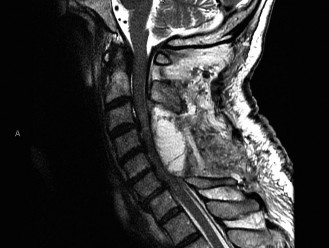

Magnetic Resonance Imaging and the Posterior Ligamentous Complex

To definitively assess the integrity of the soft tissue stabilizers and the neural elements, a Magnetic Resonance Imaging (MRI) scan without contrast was performed. Historically, textbooks propagated the "50-50-25 rule," suggesting that a burst fracture was inherently unstable if it exhibited >50% canal compromise, >50% loss of vertebral body height, or >25 degrees of kyphosis. Modern spine trauma surgery has largely debunked this rigid radiographic dogma. We now understand that these bony metrics alone do not dictate mechanical instability. The true arbiter of stability is the Posterior Ligamentous Complex (PLC).

The MRI, particularly the Short Tau Inversion Recovery (STIR) and T2-weighted sagittal sequences, provided the definitive diagnosis. The images demonstrated profound hyperintensity and discontinuity of the ligamentum flavum, the interspinous ligaments, and the supraspinous ligaments at the T12-L1 level. The facet joint capsules were also disrupted, indicated by fluid within the joints. This complete failure of the PLC means the posterior tension band is gone. Regardless of the bony parameters, this spine cannot resist physiological flexion loads. If treated non-operatively, this injury will inevitably lead to progressive kyphosis, delayed neurological deficit, and intractable pain.